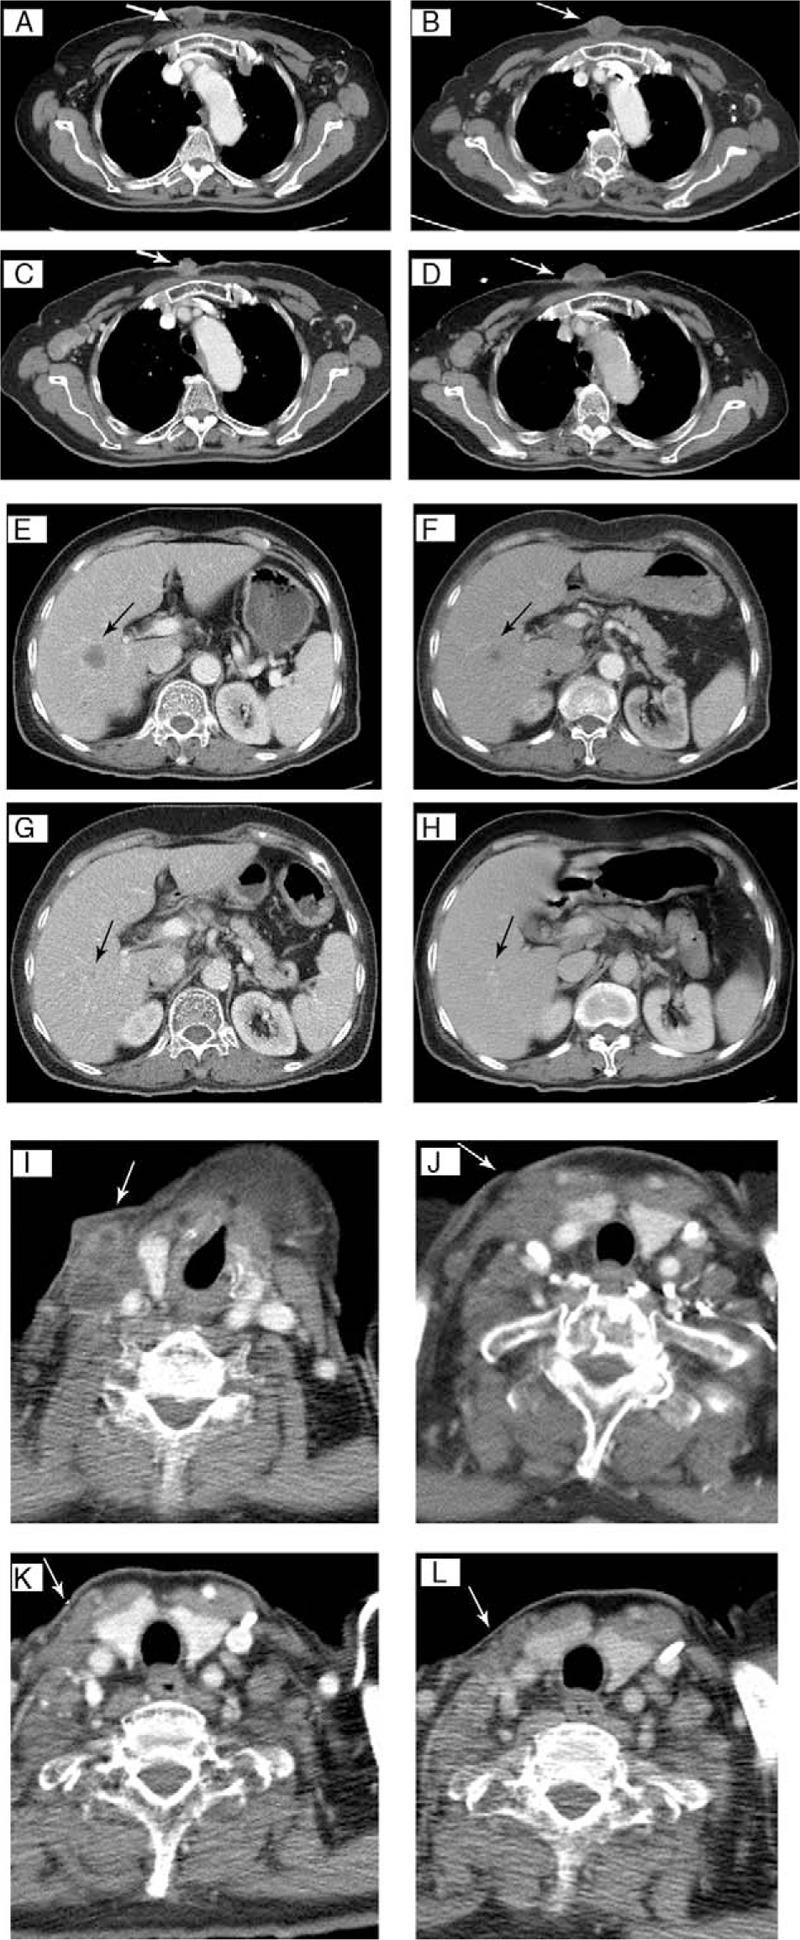

Head and neck squamous cell carcinoma (HNSCC) has a high prevalence and is a major cause of cancer deaths in Taiwan. However, there is still no effective salvage therapy that prolongs the life expectancy of patients with recurrent/metastatic (R/M) HNSCC. Immune checkpoint therapy that targets the programmed cell death protein 1 (PD-1) may provide clinical benefit for these patients. We analyzed 22 R/M HNSCC patients who received pembrolizumab, a monoclonal antibody against PD-1, as salvage therapy. Intravenous pembrolizumab was given at a fixed dosage of 100 or 200 mg every 3 weeks. Three patients also received local palliative radiotherapy, but no patients received chemotherapy or targeted drugs. Seventeen patients (77.3%) received at least 3 cycles of pembrolizumab. Based on Response Evaluation Criteria in Solid Tumors criteria (ver. 1.1), 2 patients (9.1%) had complete response, 5 (22.7%) had partial response, and 6 (27.3%) had stable disease, corresponding to a disease control rate of 59.1%. Four patients had confirmed disease progression, 2 of whom had continuous progression over the target lesion after shrinkage of other metastases. One patient developed immune-related pneumonitis that resolved quickly after steroid treatment. Another patient developed itchy skin rashes immediately after administration of pembrolizumab, and this was controlled by an antihistamine. There were no other severe adverse effects. Pembrolizumab is beneficial and well-tolerated for some patients with refractory R/M HNSCC. However, it is important to identify biomarkers to identify the most responsive patients when designing future trials.

头颈鳞状细胞癌(HNSCC)在台湾地区发病率很高,是癌症死亡的主要原因之一。然而,对于复发/转移性(R/M)HNSCC患者,仍没有有效的挽救性治疗方法能够延长其预期寿命。针对程序性细胞死亡蛋白1(PD-1)的免疫检查点疗法可能会为这些患者带来临床益处。我们分析了22例接受派姆单抗(一种抗PD-1单克隆抗体)作为挽救性治疗的R/M HNSCC患者。静脉注射派姆单抗,固定剂量为每3周100或200毫克。3例患者还接受了局部姑息性放疗,但没有患者接受化疗或靶向药物治疗。17例患者(77.3%)接受了至少3个周期的派姆单抗治疗。根据实体瘤疗效评价标准(第1.1版),2例患者(9.1%)完全缓解,5例(22.7%)部分缓解,6例(27.3%)病情稳定,疾病控制率为59.1%。4例患者疾病进展得到确认,其中2例在其他转移灶缩小后,靶病灶持续进展。1例患者发生免疫相关性肺炎,经类固醇治疗后迅速缓解。另1例患者在使用派姆单抗后立即出现皮肤瘙痒皮疹,通过使用抗组胺药得到控制。没有其他严重不良反应。派姆单抗对一些难治性R/M HNSCC患者有益且耐受性良好。然而,在设计未来试验时,识别生物标志物以确定最敏感的患者非常重要。